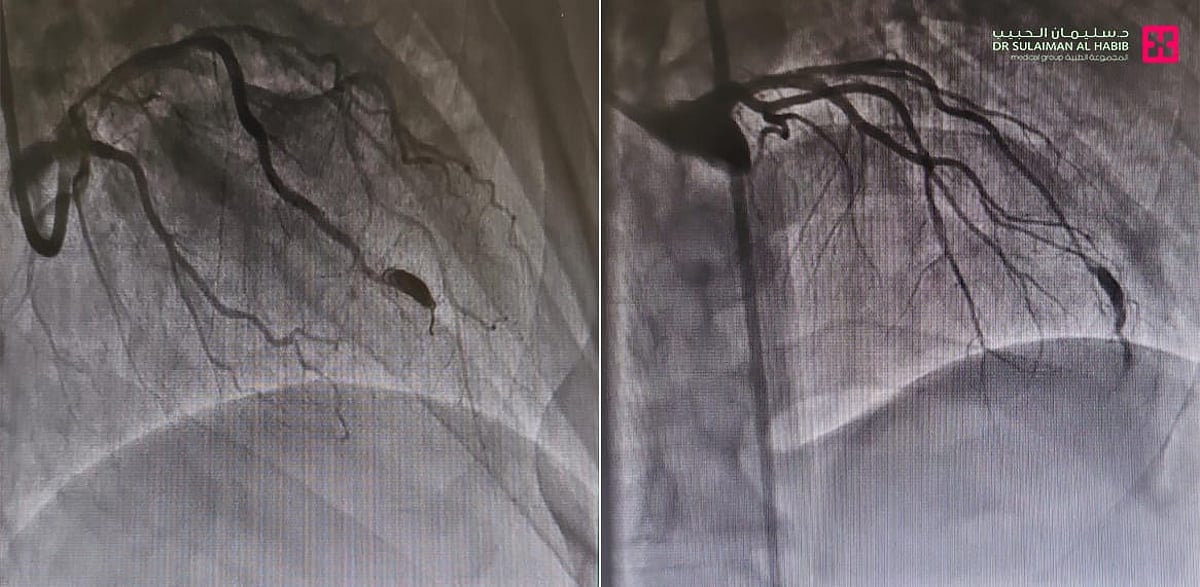

شهد مستشفى الدكتور سليمان الحبيب بالتخصصي، إجراء عملية متقدمة، لرجل يبلغ من العمر “45 ” عاماً، لإزالة انسدادات في الشرايين التاجية للقلب، واصلاح توسع في الشريان التاجي الأمامي، وأنهت العملية معاناته التي استمرت طويلاً.